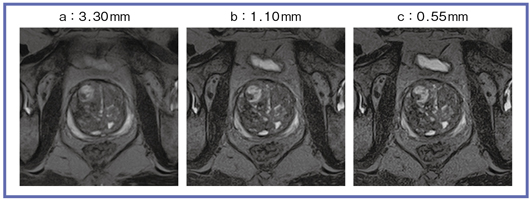

図2 FASE3D_MPVでMPRの再構成スライス厚を変化させたもの

Titan 3TのFASE3D_MPVでは,in-planeの解像度は2Dとほぼ同等で,非常に薄いスライスの画像が撮像できる。図1は,2D-FSE+JETで撮像した3mmスライスの画像との比較だが,FASE3D_MPVでは0.9mmでの撮像が可能となっている。3D-TSEでは,前立腺辺縁域の信号が高くなるため,腫瘍が明瞭に描出される。また,薄いスライスとコントラストの向上によって,移行域の結節性過形成の腺成分を反映するT2強調高信号も観察できる。今後の3Dシーケンスの調整によって,さらなる画質の向上が期待される(図2)。